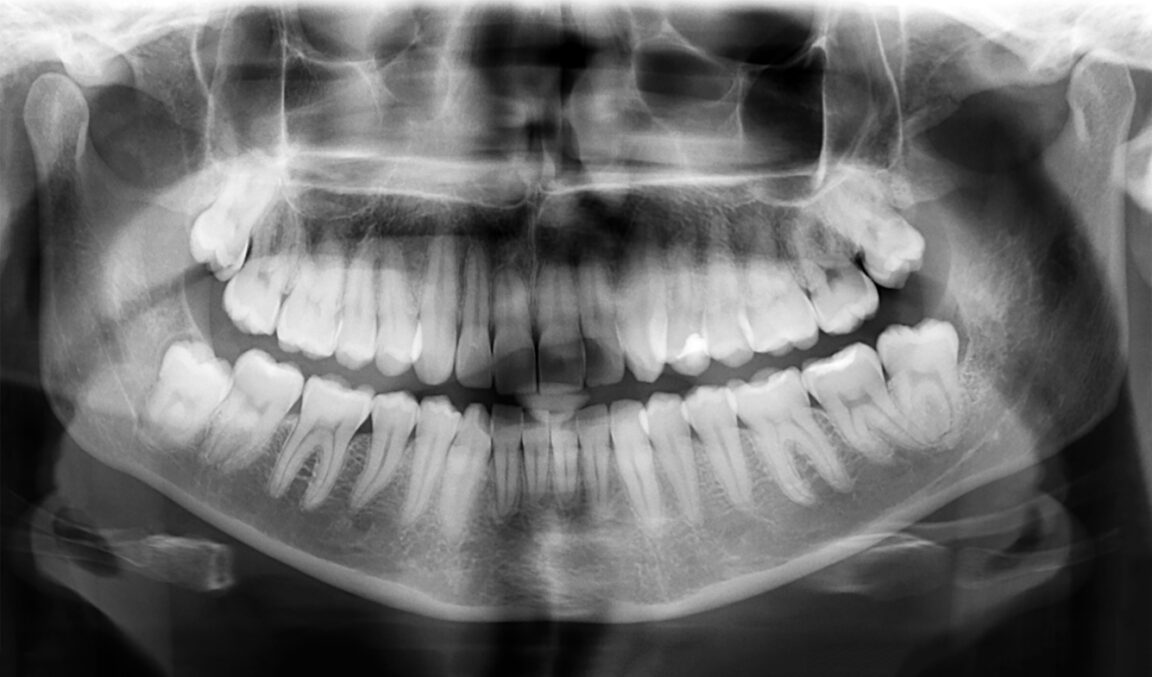

Perdre une dent peut survenir à tout âge en raison de différents facteurs : maladies congénitales, caries graves, accidents ou vieillissement. Cela engendre des conséquences importantes sur la santé buccale, la mastication et l’estime de soi.

L’humain développe naturellement deux séries de dents : les dents de lait et les dents permanentes. Toutefois, des études récentes ont mis en évidence l’existence de bourgeons dentaires dormants, présents sous les gencives. Ces bourgeons pourraient être activés pour générer une nouvelle série de dents, appelée « troisième dentition ».